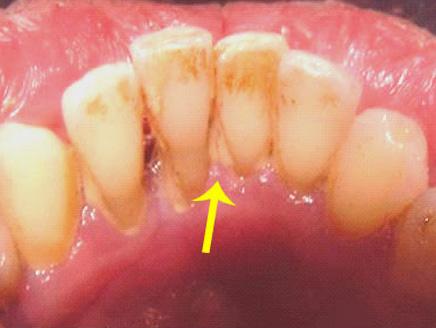

اقترب علماء هولنديون خطوة باتجاه تحسين مكافحة الترسبات الجيرية في الأسنان، حيث اكتشفوا بنية الإنزيم المسؤول عن إطلاق البكتيريا المكونة للجير والذي يجعل الجراثيم تلتصق بالأسنان وتتراكم فوقها.

وقام العلماء باستخلاص الإنزيم المسمى "جلوكانسوكريس" من أحد الأحماض اللبنية في الفم واللعاب، ثم توصلوا إلى معرفة بنيته ثلاثية الأبعاد.

ويتكون نفس الإنزيم من بكتيريا ستريبتوكوكوس موتانز، أحد المسببات الأساسية لتسوس الأسنان.

وهذه البكتيريا مسؤولة عن تحويل سكر السكروز الذي يتناوله الإنسان في غذائه إلى مادة الجلوكوز السكرية أو مادة الفركتوز قبل أن يتم ربط جزيئات الجلوكوز في سلسلة تمكن البكتيريا من الالتصاق باللثة.